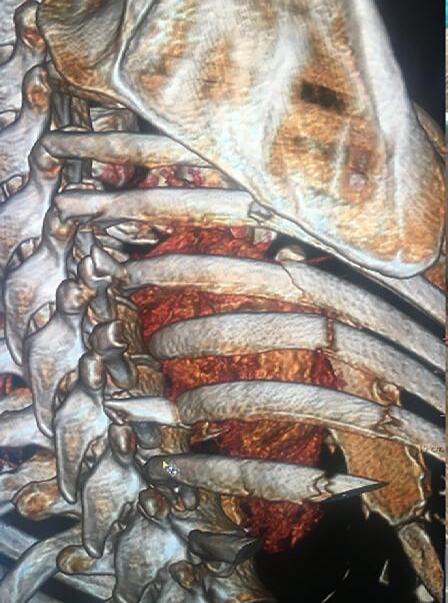

At our institution, all patients with rib fractures were admitted to a trauma ICU ward and offered the standard of care as per protocol of the unit, including intravenous analgesia; oxygen, nebulised bronchodilators as needed, mechanical ventilation when indicated, management of associated injuries and active physiotherapy. A computed tomography scan (CT) of the chest was obtained and three-dimensional (3-D) volume reconstructions performed to evaluate the thoracic skeleton and assess indication for surgery.

The surgical procedure to fix the ribs was performed using a muscle sparing thoracic incision (Figure 1). The ribs were stabilised using titanium plates and screws (RibFix BluTM, Zimmer Biomet, Jacksonville, USA); an effort was always made to provide stability for all accessible fractures.

Figure 1: A typical example of multiple rib fractures and three plated fractures

sixty per cent of the cases were considered severe trauma (ISS > 16), the median ISS was 21 (4–75). For the patients treated with BMT, the median ISS was 24 (4–75) versus ISS 21 (16–75) for those offered surgery (Table 2).